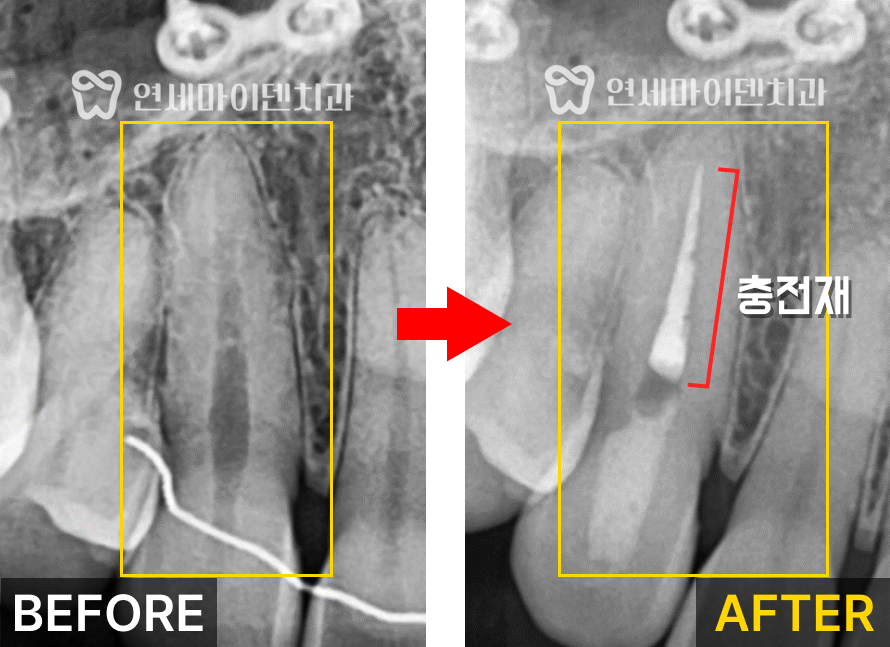

내부로 신경이 괴사된 유기물이 많이 보이는게 확인됩니다.

지저분한 유기물들을 제거하고 괴사된 신경을 제거하였습니다.

많은 유기물들로 가득차있던 내부가

신경치료 후 확연히 깨끗해진 것이 보입니다.

제거한 신경관 내부에는 신경 충전재를 채워서 신경치료를 마무리 합니다.

여기서 심미적인 결과를 위해 가장 중요한 것은

신경 충전재를 적절한 위치까지 끊어주는 것입니다.

신경치료 시 충전재를 치아 머리까지 채워버리면

이후 변색이 발생할 가능성이 높아집니다.

세심한 테크닉으로 필요한 부분까지만 충전재를 채워주어야

신경치료 후에도 변색없이 유지할 수 있습니다.

충전재를 적절한 위치까지만 채워준 뒤

실활치 미백을 진행해서 변색된 치아를 밝혀주었습니다.

이후 레진코어로 구멍을 메워준 뒤 치료를 마무리 했습니다.